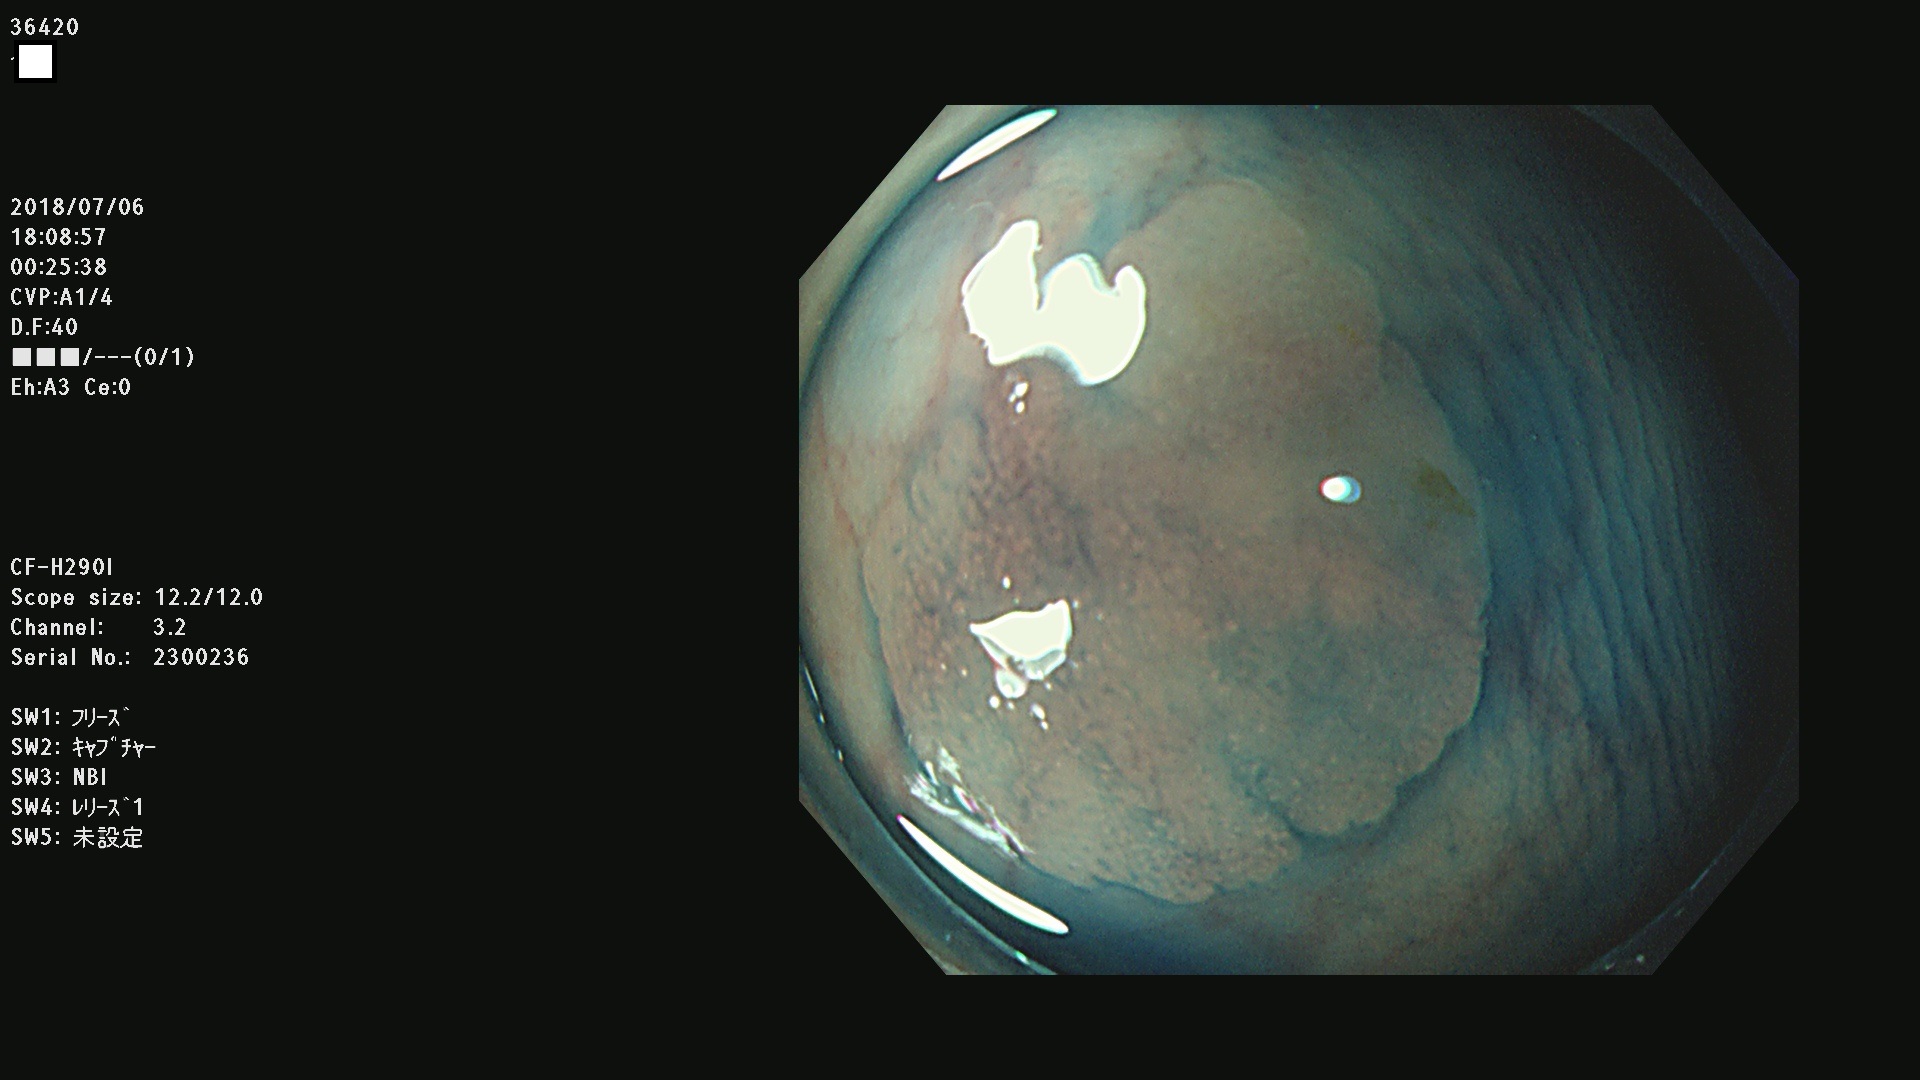

36400(SSAPのみ) 36402 36403 36404 36405 36406 36407 36408(SSAPのみ) 36412 36413 36414 36415 36416 36417 36418 36420 36422 36423 36424 36425 36426 36428 36429 36430 36431 36434 36435 36436 36437 36438 36440 36443 36447 36448 36449 36450 36452 36454 36458 36459 36460 36462(SSAPのみ) 36463 36464 36465 36466 36470 36471 36472 36473 36474 36475 36476 36478 36480 36481 36482 36484 36487 36488 36489 36490 36492 36494 36495 36496 36497 36498

発見困難で危険性の高い平坦型病変(上記100名より抽出)